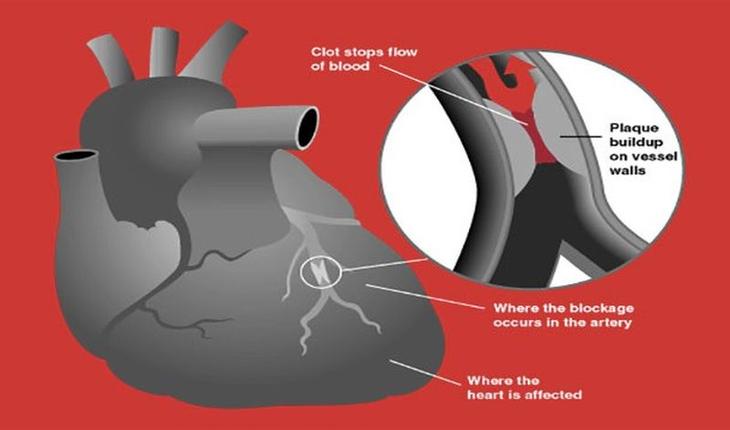

13) Даже с сердцем связаны некоторые различия. Например, симптомы сердечного приступа у мужчин довольно четкие: по ним сразу понятно, что происходит. Что же касается женщин, симптомы сердечного приступа могут быть гораздо более неожиданными, настолько, что не всегда понятно, что же происходит с несчастной.